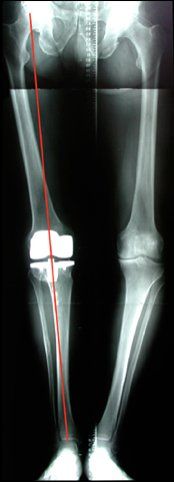

Les prothèses totales : ont pour but de remplacer les 3 compartiments du genou, réaxer la jambe et récupérer la mobilité du genou en particulier l’extension lorsqu’elle est déficitaire. Au cours de cette intervention les ligaments croisés sont le plus souvent sacrifiés, mais les ligaments latéraux et l’enveloppe globale du genou est préservée. L’absence des ligaments croisé sera compensé dans le dessin de la prothèse afin de stabiliser et favoriser le fonctionnement de la prothèse tout en limitant tant que possible de solliciter ses ancrages.

On recherche essentiellement à l’examen : une désaxation de la jambe constitutionnelle mais aussi liée à l’usure du cartilage, une perte de mobilité en particulier de l’extension, une perte musculaire (amyotrophie) qui traduit une sous utilisation du genou. On détermine également un retentissement du genou atteint sur le dos, la hanche ou la cheville.

L’étude des radiographies analyse la déformation réelle, les articulations sus et sou jacente et le degré d’usure. Il est important de préciser que l’indication de prothèse se pose dans la majorité des cas devant un bilan radiologique standard. Une IRM ne doit donc pas être le principal examen.

Désaxation et perte d’extension